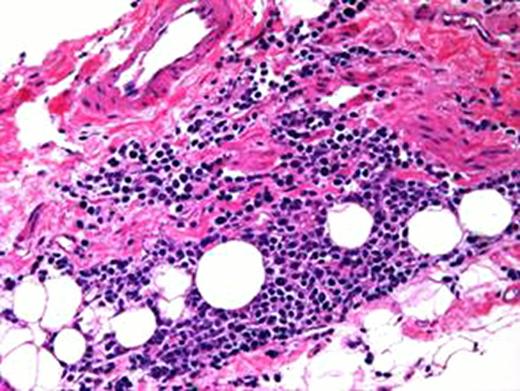

Right kidney TMA at x20

She failed to respond to various agents including corticosteroids and therapeutic plasmapheresis and died 44 days after the single CFZ dose. Repeat serum myeloma markers showed response to CFZ. Autopsy examination revealed TMA with presence of red blood cell fragments and multiple fibrin thrombi in the kidneys without evidence of amyloidosis or plasma cell infiltration. Aggregates of CD 138 positive plasma cells were present in the visceral pleura of the stomach, bladder, pancreas and intestines but without organ infiltration. The bone marrow was hypercellular with 5% involvement with lambda predominant plasma cells. At death, the serum levels of lambda light chains and IgG were 54. 8 and 1000 mg/dL, respectively.